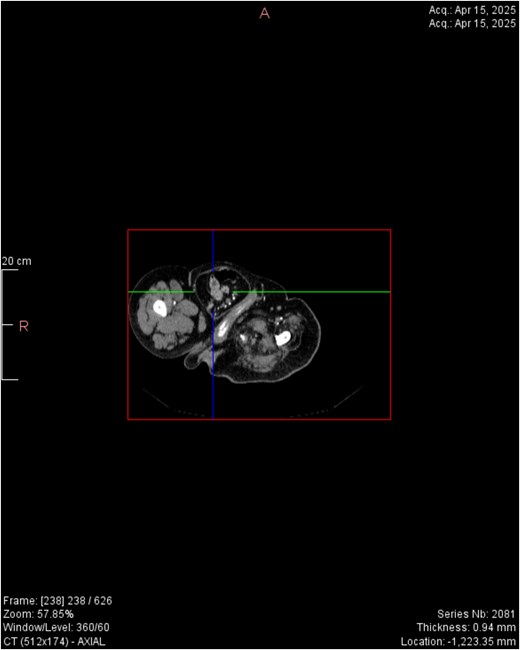

CT imaging (Figs 2–5) revealed a right inguinal hernia containing small bowel loops, ascending colon, the second and third portions of the duodenum, and the pancreatic head. The pancreatic head appeared rotated and displaced inferiorly into the hernia sac, without signs of acute pancreatitis.

Horizontal CT view inguinal hernial sac with pancreatic head and D2 and D3 segment of duodenum.